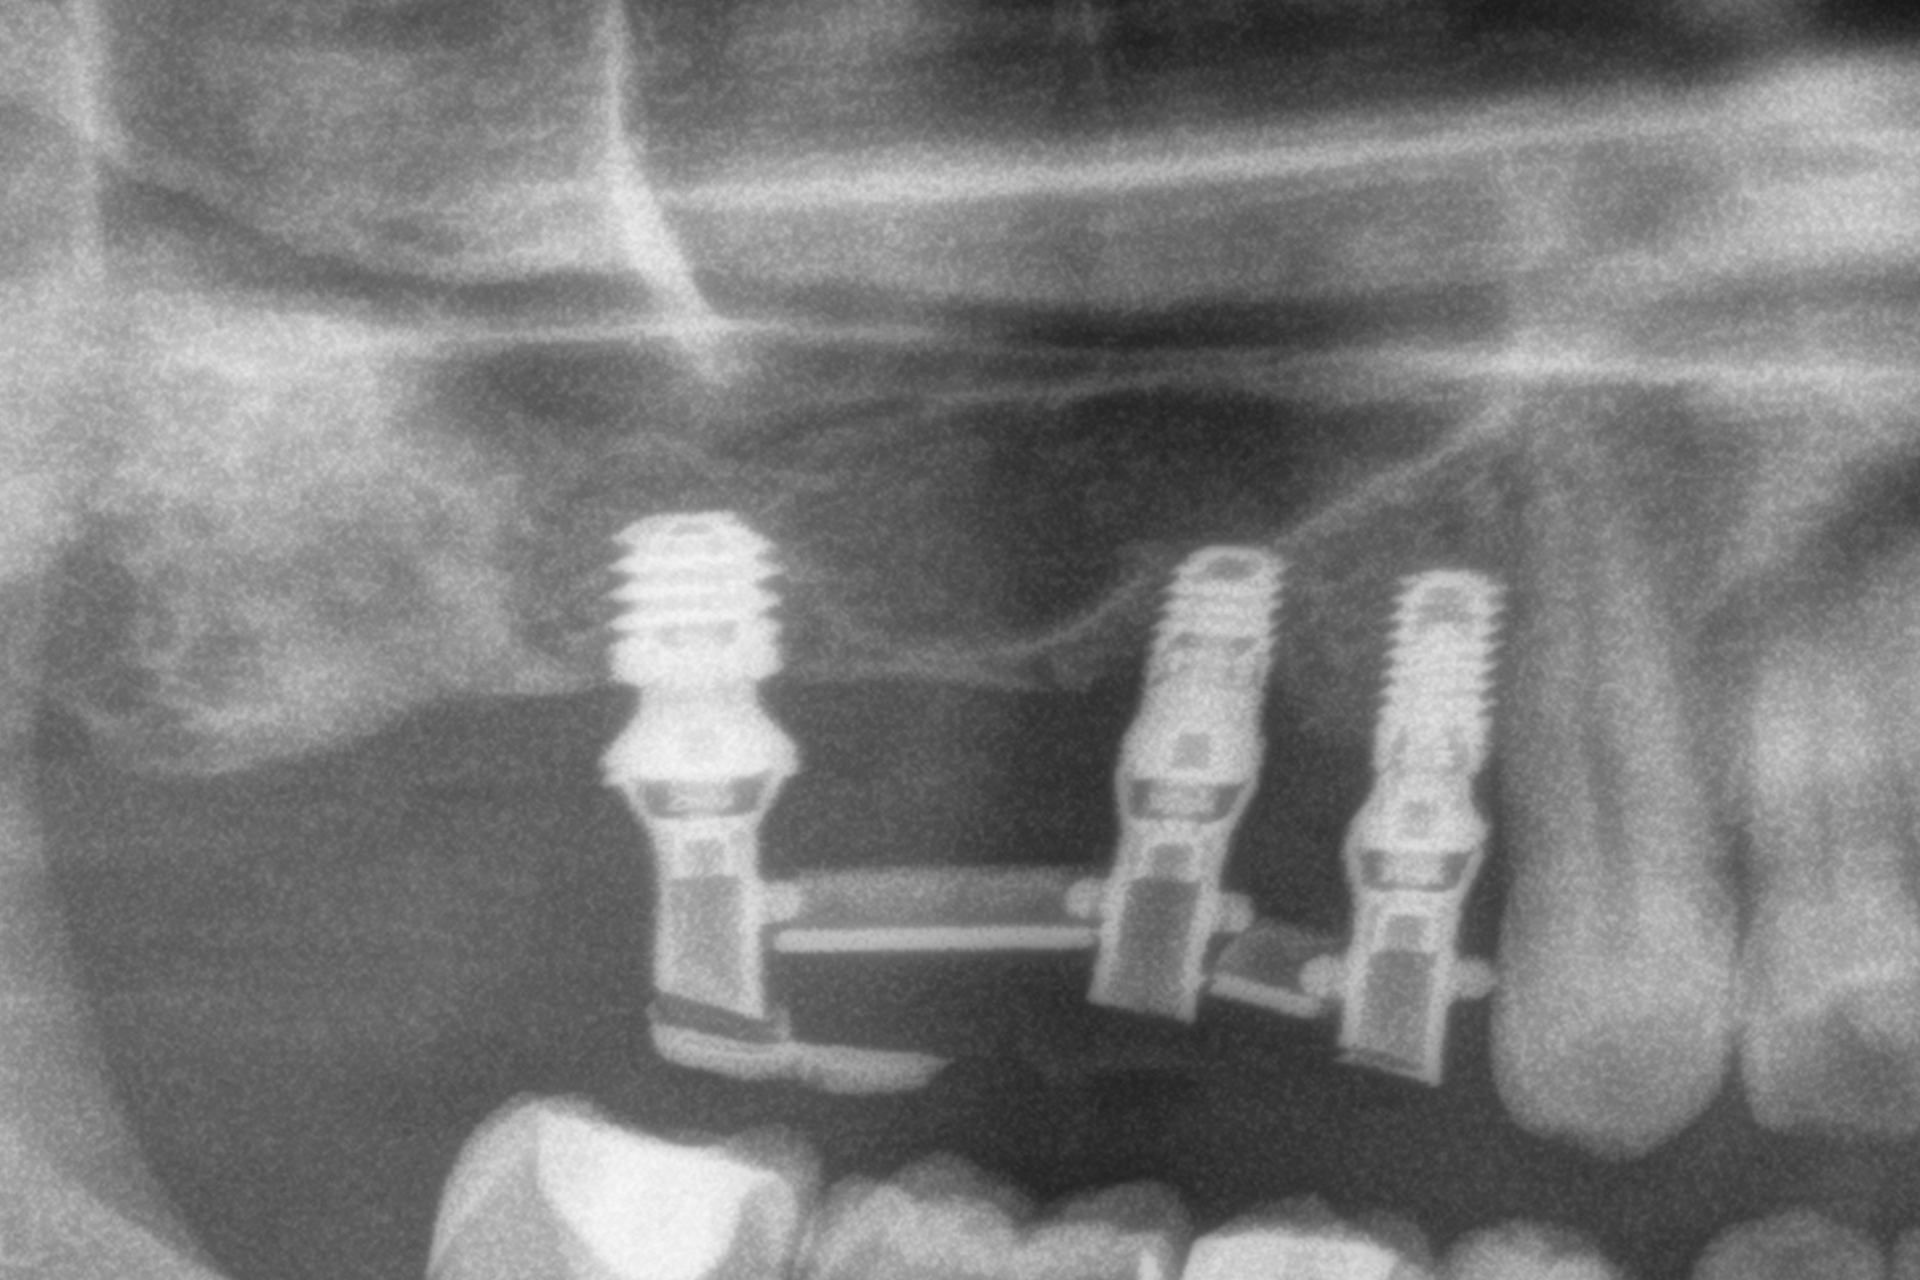

Tutti gli impianti sono stati caricati entro 24 ore dall’inserimento mediante protesi provvisorie in resina a carico immediato, realizzate con strutture a barra articolata. L’analisi dei diversi tipi di protesi ferulizzate ha evidenziato una predominanza delle riabilitazioni parziali. Il gruppo più numeroso era costituito dalle protesi supportate da due impianti e due elementi dentari, pari al 33,3% dei casi, seguito dalle protesi complete, presenti nel 19,4% dei pazienti. Altri disegni protesici sono stati utilizzati con frequenze comprese tra l’8,3% e il 16,7%, riflettendo l’adattamento del piano terapeutico alle specifiche condizioni anatomiche di ciascun paziente, mantenendo in tutti i casi la ferulizzazione rigida degli impianti come principio biomeccanico fondamentale (Figura 1).

In 19 impianti sono state eseguite procedure complementari contestualmente all’inserimento implantare: in due casi rigenerazione verticale con osso autologo da fresaggio associato a PRGF-Endoret; in 11 casi rialzo del seno mascellare transalveolare con osso autologo e PRGF-Endoret; in sei casi sovracorrezione vestibolare mediante osso autologo e PRGF-Endoret, associando uno strato di biomateriale (idrossiapatite bovina) per ridurre il riassorbimento volumetrico. Quattro impianti da 4,5 mm sono stati ferulizzati ad altri impianti della stessa lunghezza, per un totale di otto impianti ultra-corti ferulizzati tra loro, configurando ponti supportati da tre impianti. La protesizzazione definitiva è stata eseguita tra tre e nove mesi dopo il carico immediato. Le protesi definitive erano in metallo-ceramica nell’80,6% dei casi e in resina con struttura metallica nei restanti.

Durante il periodo di osservazione non è stato registrato alcun fallimento implantare, con una sopravvivenza del 100%. Non sono state riportate complicanze chirurgiche e sono state osservate solo quattro complicanze protesiche, tutte rappresentate da allentamento delle viti nella fase di protesi definitiva; pertanto, anche la sopravvivenza protesica è risultata del 100%. Il follow-up medio è stato di 38,5 ± 3,60 mesi, con un intervallo compreso tra 12 e 60,5 mesi.

Al termine del follow-up, la perdita ossea crestale media è stata di 0,73 ± 0,18 mm in mesiale e di 0,85 ± 0,34 mm in distale. Alcuni casi clinici rappresentativi sono illustrati nelle Figure 2-10.